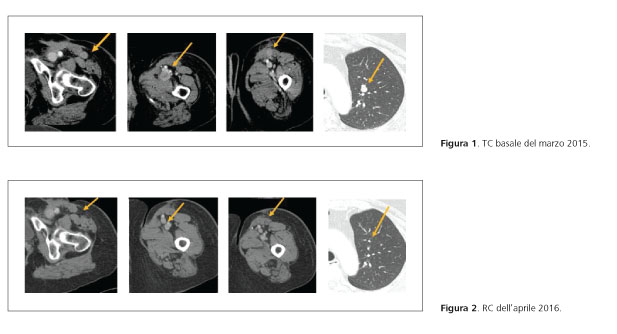

La paziente accettava l’arruolamento nel protocollo COLUMBUS e veniva randomizzata al braccio di trattamento combinato con encorafenib 450 mg/die e binimetinib 45 mg ×2/die. La TC basale documentava multipli noduli polmonari (il maggiore di 10 mm al lobo superiore di sinistra), muscolari (il maggiore di 25 mm nel contesto del muscolo sartorio) e sottocutanei (il maggiore di 10 mm sul versante antero-mediale della coscia, caudalmente alla cicatrice chirurgica) (figura 1).

Dalla prima rivalutazione, effettuata dopo 2 cicli di trattamento, si osservava una riduzione maggiore del 50% di tutte le lesioni, con l’ottenimento di una remissione completa al controllo del aprile 2016, dopo 13 cicli di trattamento (figura 2).